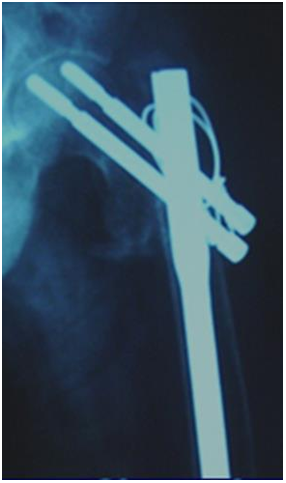

Hip pin and compression screw

Hip pin to be shorter than compression screw. Deep positioning to maintain tip apex distance. Head screws to be tightened alternately for compression. But may sink inside bone (Figure 31,32).

Figure 31 Hip pin to be shorter than compression screw. Deep positioning to maintain tip apex distance.

Figure 32 Head screws to be tightened alternately for compression. But may sink inside bone.